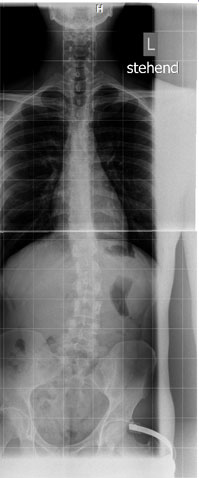

Lange Rede, kurzer Sinn: heute bin ich dann zum Röntgen gegangen (mein Orthopäde hatte eine Thoracolumbalskoliose diagnostiziert und mich zum Röntgen überwiesen) und habe das Bild auf CD mitbekommen. Es wird noch etwas dauern bis ich einen neuen Termin bekomme und einen Befund zu dem aktuellen Bild bekomme - ich habe also noch nicht Rückspräche bezüglich der Aufnahmen mit meinem behandelten Arzt nehmen können. Natürlich bin ich dennoch neugierig.

Ich muss sagen, wenn ich das aktuelle Bild mit denen von 2006 vergleiche (hier kann ich nur "Rückgriff" auf meine Erinnerungen bzgl. der Aufnahmen nemen, aber habe ja den Befund von damals vorliegen s.o.), so ist es subjektiv sogar BESSER! geworden. Ich kann auf den Röntgenaufnahmen in der oberen Hälfte meiner Wirbelsäule keine deutliche Verkrümmung erkennen. In der unteren Hälfte vermag ich in jedem Falle eine recht deutliche Skoliose und einen Beckenschiefstand zu erkennen.

Anbei das Röntgenbild vorhin. Was meint ihr? Ist es im Vergleich zu meinem damaligen Befund besser/schlechter/unverändert geblieben? Wie hoch meint ihr ist der Cobb-Winkel?

Man kann unmöglich einen Befund ohne Winkelangaben mit diesem Röntgenbild vergleichen. Bei Winkel-Abschätzungen halte ich mich generell zurück. Aber besonders "schlimm" finde ich es nicht.Anbei das Röntgenbild vorhin. Was meint ihr? Ist es im Vergleich zu meinem damaligen Befund besser/schlechter/unverändert geblieben? Wie hoch meint ihr ist der Cobb-Winkel?

Jedoch scheint mir auf dem Röntgenbild die BWS recht grade zu sein und der Bogen in der LWS ist ja auch nicht sonderlich stark.

Wahrscheinlich sind es bei dir eher die Beckenschiefstellung und die Spondylose die Probleme bereiten?!